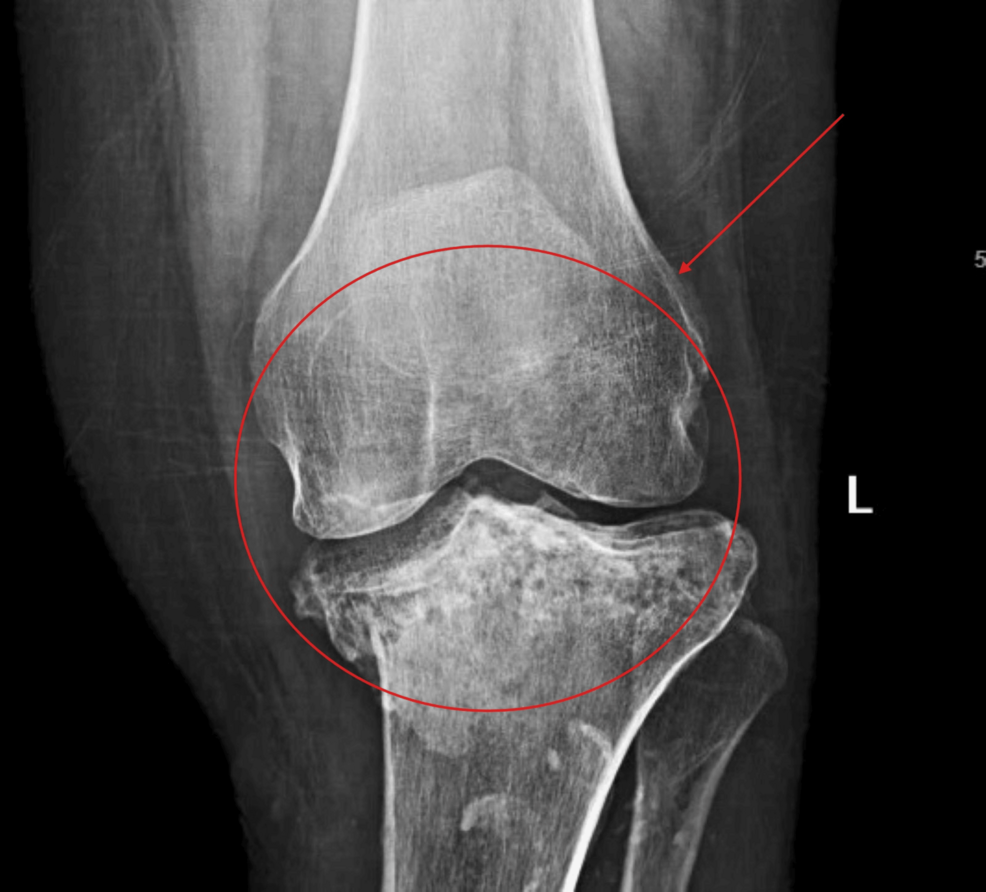

The case involved a 54-year-old male with a history of sarcoma who had previously undergone radiation therapy. He presented with knee effusion—an abnormal accumulation of fluid in the joint—which served as an early warning sign of a deeper, more systemic failure of the bone tissue. What began as joint swelling evolved into a chronic bone infection and a structural collapse of the limb, necessitating an aggressive multidisciplinary surgical intervention.

In the context of post-radiation recovery, a swollen joint is rarely just a sign of wear and tear. In this patient’s case, the knee effusion was the primary clinical indicator that something was wrong beneath the surface. When fluid builds up in the joint space, it often signals inflammation, injury, or infection.

For patients with a history of radiation, this inflammation can be a harbinger of osteoradionecrosis—a condition where bone tissue dies due to radiation-induced damage to the blood supply. This necrotic tissue becomes a breeding ground for bacteria, as the compromised blood flow prevents the body’s immune cells and systemic antibiotics from reaching the site of infection effectively.

The progression from effusion to a pathologic fracture is a critical window for intervention. A pathologic fracture differs from a standard break due to the fact that it requires very little trauma to occur. the bone is so structurally compromised by the underlying osteomyelitis and radiation damage that it can fail under the stress of normal daily activities.